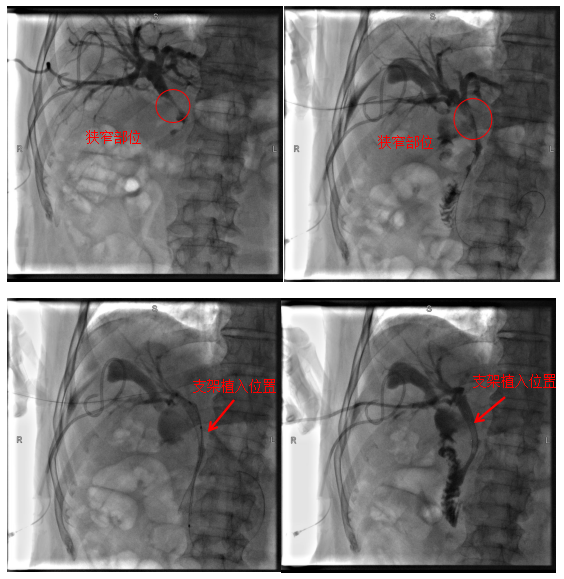

病例2

患者為72歲老年男性,因“右上腹疼痛2月,眼黃、尿黃1周”入院。入院后完善相關(guān)檢查考慮膽管中段惡性腫瘤、梗阻性黃疸,患者心肺功能極差,心血管內(nèi)科、呼吸與危重癥醫(yī)學(xué)科及麻醉科會(huì)診評(píng)估后考慮患者無(wú)法耐受全身麻醉,肝膽胰外科團(tuán)隊(duì)充分評(píng)估后決定為患者行經(jīng)皮經(jīng)肝膽道支架植入術(shù),手術(shù)順利,術(shù)后患者黃疸逐漸消退,有效地改善了患者的生活質(zhì)量,延長(zhǎng)了患者的生存時(shí)間。

術(shù)中影像